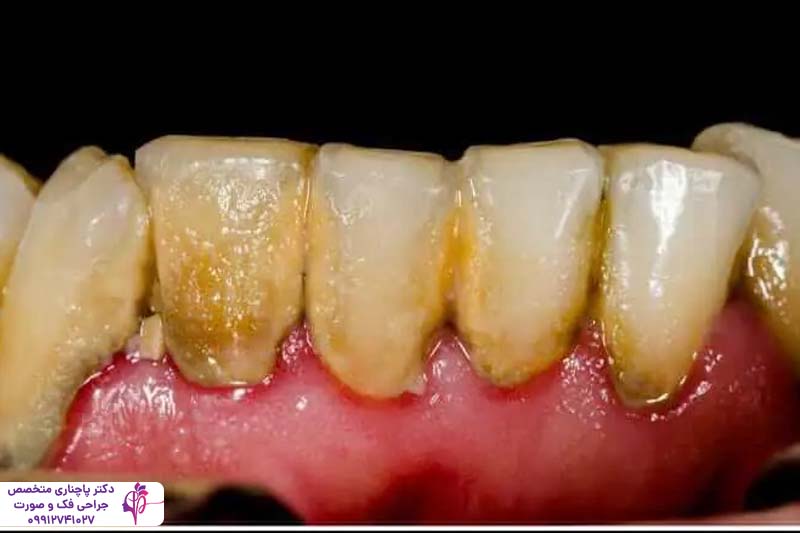

پریودنتیت

پریودنتیت مرحله پیشرفتهتر و جدیتر بیماری لثه است که در صورت عدم درمان ژنژیویت ایجاد میشود. در این مرحله، عفونت باکتریایی از سطح لثه به بافتهای عمیقتر، از جمله استخوان نفوذ میکند. باکتریها باعث ایجاد کیسههای عفونی یا کیسههای پریودنتال بین دندان و لثه میشوند و به تدریج به عمق بافت لثه نفوذ میکنند و باعث تجمع بیشتر پلاک و جرم میشوند. این مرحله از بیماری پریودنتال به تدریج باعث تخریب بافت لثه و استخوان میشود و در موارد حاد حتی با عقب راندن لثه باعث شل شدن دندانها و رد نهایت افتادن آنها میشود.

این مرحله از بیماری خودش را با خونریزی مداوم لثه، بوی بد دهان و حساسیت شدید دندانها به گرما و سرما و حتی درد در هنگام جویدن نشان میدهد. این مشکل در موارد شدید بافت لثه را کامل از بین میبرد و ریشه دندان نمایان میشود. بر خلاف ژنژیویت این مشکل نیاز به درمان حرفهای از طرف دندانپزشگ دارد. درمان بیماریهای لثه قبل از ایمپلنت در این مرحله شامل تمیز کردن عمیق توسط دندانپزشک، جراحی لثه یا حتی استفاده از آنتیبیوتیکهای قوی میشود. برای بیمارانی که قصد انجام ایمپلنت دارند درمان این مرحله از بیماری لثه قبل از ایمپلنت اهمیت زیادی دارد چون عفونت فعال باعث التهاب در اطراف ایمپلنت میشود و در نتیجه کاشت با شکست مواجه میشود.